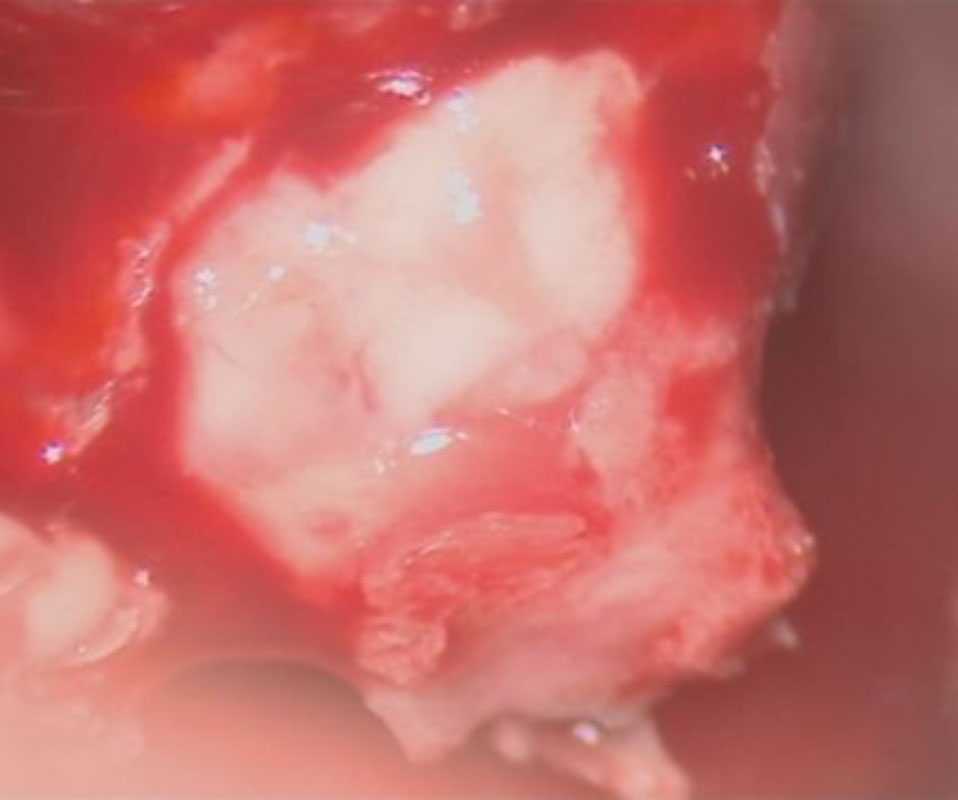

No.’25_74 摘出 前

No.’25_74  摘出 中